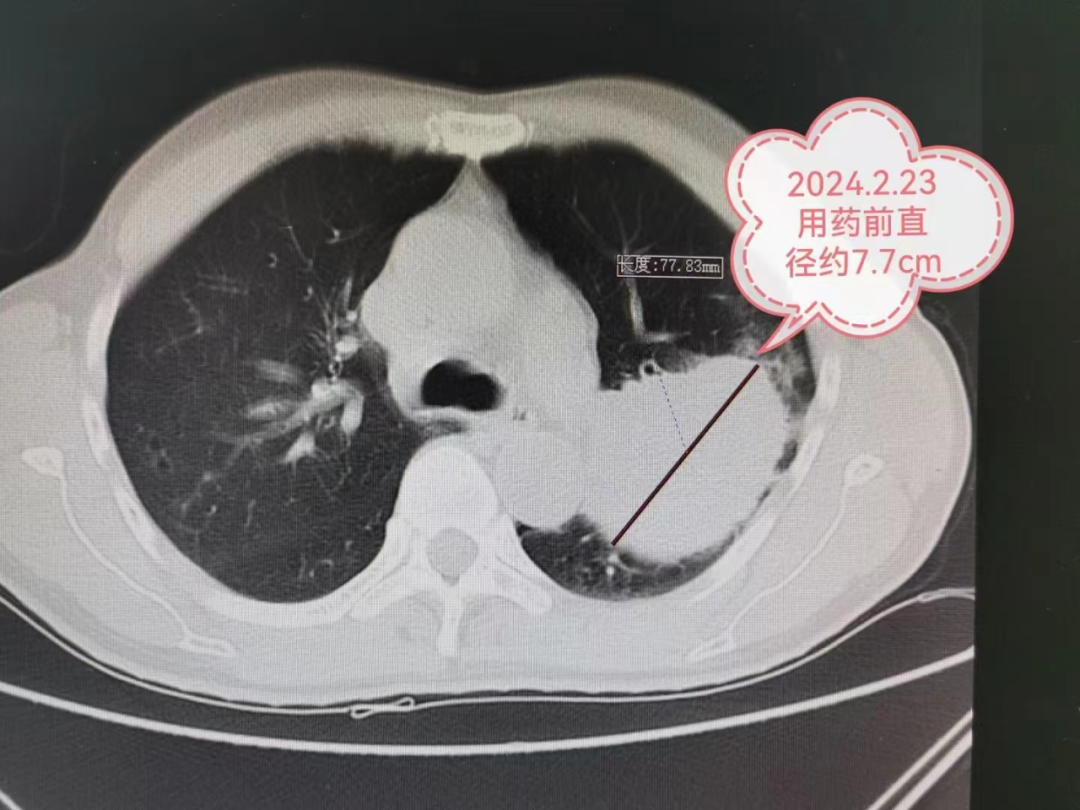

肺癌是我国发病率和病死率最高的恶性肿瘤,其中非小细胞肺癌约占肺癌的80%-85%。肺癌的治疗原则是以外科手术为首选的综合性治疗,所以,外科手术是治疗肺癌的首选方法。早期肺癌并行根治性手术,5年生存率可达90%以上。然而约60%的肺癌临床确诊时已处于局部晚期或转移性晚期,错失了手术治疗的时机,既往只能采用放射治疗(放疗)或化学药物治疗(化疗)及联合放化疗的治疗方式,但效果并不理想。 近年来由于基因靶向治疗、免疫治疗等先进治疗手段的出现,术前新辅助治疗在偏晚期肺癌的治疗中取得了很好的疗效,偏晚期肺癌得到降期而获得手术机会。下面,我们来看一个实际的例子: 今年2月严先生因 “ 反复咳嗽、咳痰3年, 病情加重伴气促2月” 到贵州航天医院就诊, 经胸部CT检查发现左肺上叶占位, 肺穿刺病理确诊为左上肺鳞癌, 肿瘤大小约为66mm×77mm, 且肿瘤包裹左上肺重要血管。 贵州航天医院肺癌MDT(多学科会诊)团队开会讨论,考虑肺癌分期较晚,暂无手术机会,决定先给予3-4个周期的新辅助化疗+免疫治疗后,再判断有无手术机会。 经过4个周期的新辅助化疗联合免疫抑制治疗后,肿瘤最大直径由77mm明显缩小到40mm,分期由IIIA期降为IIA期。 心胸外科陈光春主任团队召开病例讨论会,大家一致认为新辅助化疗联合免疫抑制治疗效果明显,患者获得了根治性手术机会。经过严谨、全面的术前准备后,最终为严先生成功实施单孔胸腔镜下肺癌根治术,手术圆满成功。 术后5天,严先生已恢复日常生活能力,严先生及其家人感叹术前的4个周期化疗+免疫治疗加上单孔胸腔镜微创手术,最终让“心里一颗大石头放下了”。 术后病理检查显示:经过之前的新辅助治疗,病变的大小由77mm缩小到40mm(缩小约48%),经过显微镜观察,实际的癌细胞仅仅残存6%,也就是说40mm肿块里面94%的组织已经没有癌细胞啦,医学上称这种情况叫做主要病理学缓解(MPR)。 有研究显示经过新辅助治疗,约50%甚至更多患者可以达到主要病理学缓解(MPR)。如果新辅助治疗后病理检查提示病灶已经没有癌细胞了,称之为完全病理学缓解(PCR)。 写到这里,可能大家会有些疑问,我们来总结回答一下: 什么是辅助治疗? 辅助治疗是指术后继续使用化疗、放疗、靶向、免疫等手段巩固治疗,降低复发可能性。但并不是所有患者都需要进行辅助治疗,需依据患者的术后病理确定,如肺腺癌的患者,手术后确定是病理类型良好的Ⅰa期,则术后定期随访观察即可,一般无需进行辅助治疗。 什么是新辅助治疗? 新辅助治疗是指术前接受化疗、放疗、靶向、免疫等治疗手段,使得肿瘤变小,实现降期,使得患者获得手术机会,并获得更好的效果。术前免疫治疗还可能通过免疫作用清除微转移灶,从而实现预防肿瘤复发转移的作用。 新辅助治疗具有两大优势:一方面,对于部分没有手术机会的患者,通过新辅助治疗获得手术机会,降低手术难度和风险,提高手术根治率;通过缩瘤减少手术的切除范围,提高患者术后生活质量;另一方面,通过新辅助治疗消灭常规影像学检查不能测到的微小转移灶,降低术后复发及远处转移的可能。例如:存在腋窝淋巴结转移的乳腺癌患者,直接手术复发风险较高,可先进行6个周期的新辅助化疗或者新辅助化疗联合靶向治疗,然后再手术,此时效果相对较好且复发风险较低。 为什么过去的晚期肺癌 不做手术? 在过去,没有基因靶向治疗和免疫治疗,只有化疗、放疗。放化疗的抗肿瘤作用比较有限而副作用又比较大。副作用大,能够使用时间就短,更多疗程的术前放化疗病人是无法耐受的。本来效果就有限,然后病人能够承受的治疗疗程又特别短,这种情况下术前放化疗很难达到满足手术要求的疗效(比如:肿瘤缩小到被肿瘤包裹的血管能够在手术时暴露处理),所以在那个年代,晚期肺癌是做不了手术的。 为什么现在的晚期肺癌 有机会手术了? 新出现的基因靶向治疗和免疫治疗特点:副作用小,患者才可以长期使用;药物有效率高,使用以后肿瘤就容易变小甚至消失。所以,基因靶向治疗和免疫治疗以更高效的速率杀灭肿瘤细胞,原本一个非常广泛发展的肿瘤,可以被安全地缩小到一定程度范围,而且还不会伤及身体的根本。 手术不再是晚期患者不可企及的奢望,而是顺其自然地照进了现实。比如本文中的IIIA期肺癌患者,且肿瘤包裹左上肺重要血管,几乎没有手术机会,或者被迫切除左全肺,术后生活质量差。在免疫药+化疗药的协同作用下,肿瘤直径缩小48%,分期由IIIA期降为IIA期,于是手术机会来了,而且只切除了左上肺,保留住了左下肺,术后生活质量相对切除左全肺更好。手术切除后肿瘤残余比例不足10%,实现了主要病理缓解(MPR)。 贵州航天医院心胸外科简介 心胸外科是诊治疾病种类较为复杂,专科性非常强的一门学科。心胸外科手术难度大,风险高,对设备和配套要求也高,大众对心胸外科经常会存有误解,误认为心胸外科只是看胸外面的病,这就很容易让人联想到乳腺疾病等,其实胸外科主要看的是胸腔内的病,主要是食管、气管及肺上的疾病。如食管囊肿、食管平滑肌瘤、贲门失迟缓症、严重的反流性食管炎、食管裂孔疝、自发性食管破裂、食管、气管瘘、食管癌、食管胃交界处癌(贲门癌)、肺大疱(有时破裂引起自发性气胸)、肺脓肿、肺隔离症、肺结核球、肺结节等需到心胸外科就诊。 心胸外科导航 贵州航天医院呼吸综合楼003诊室 住院病区:呼吸综合楼4楼 门诊坐诊时间 每周一至周五每周一至周五 (08:00—12:00;14:00—17:00) 咨询电话 住院病区咨询电话:27677360(医生办公室);0851-27677732(护士站) 心胸外科专家 注:部分图片来源于网络,如有侵权,请联系删除。 供 稿:陈光春(心胸外科) 编 辑:唐语蔚 一 审:陈光春 二 审:陈 伟 三 审:蒙昌耀